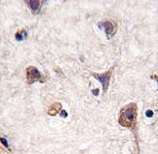

Supportive validation

- Submitted by

- Arigo (provider)

- Main image

- Experimental details

- Immunohistochemistry: human brain tissue stained with ARG54709 anti-LC3A antibody.